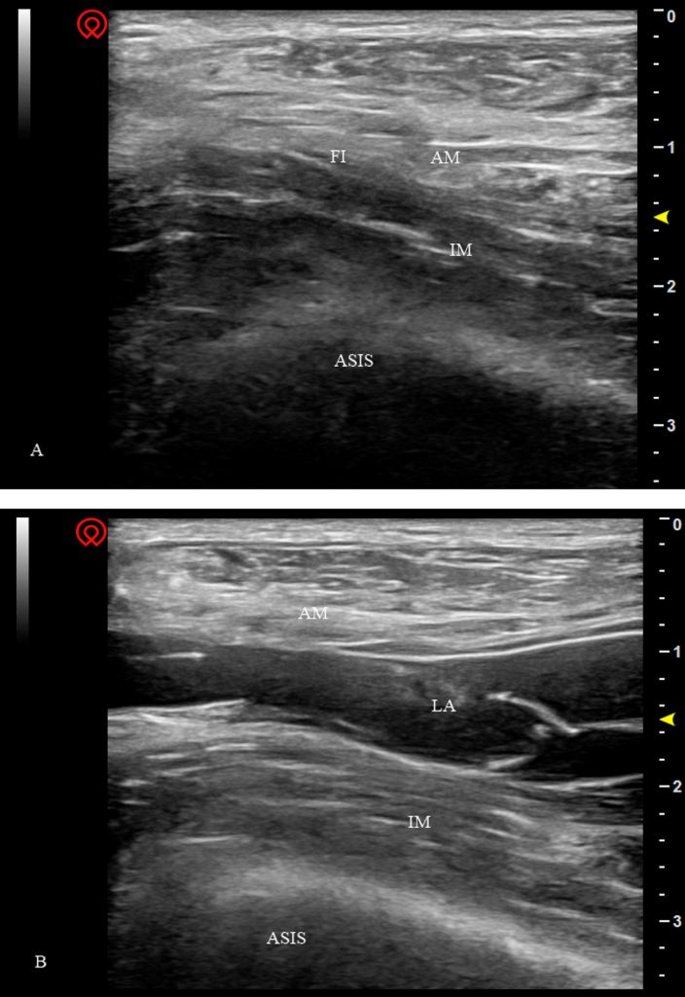

On the day of admission, appropriate supra-inguinal FICB was performed in the ward under sterile technique using a Wisonic Clover 50 ultrasound device (Huasheng Medical Technology Co., Ltd., Shenzhen, China). With the patient in the supine position, a high frequency (5–13 MHz) linear probe was placed longitudinally at the level of the anterior superior iliac spine (ASIS) and slid in a medial and caudal direction. After identifying the iliacus muscle (IM), abdominal muscles (AM) and fascia iliaca (FI), the cranial end of the probe was rotated slightly towards the umbilicus until the deep circumflex iliac artery was visualised on the screen. Using an in-plane technique, an 8-cm 22-gauge insulated block needle (Tuoren™, Tuoren Co. Ltd., Henan, China) was then inserted from the caudad side and directed cephalad, penetrating the fascia iliaca and injecting 3 mL of saline to separate the fascia iliaca from the iliac muscle. The predetermined concentration of 30 mL of ropivacaine was injected (Fig. 1). To avoid local anesthetic toxicity, the maximum dose of ropivacaine administered to all the participants was less than 3 mg/kg. Vital signs including heart, noninvasive blood pressure, respiratory rate and pulse oximetry were continuously monitored throughout the procedure.